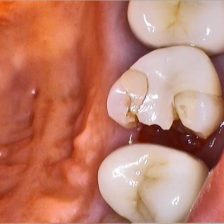

虫歯治療

メタルフリー治療